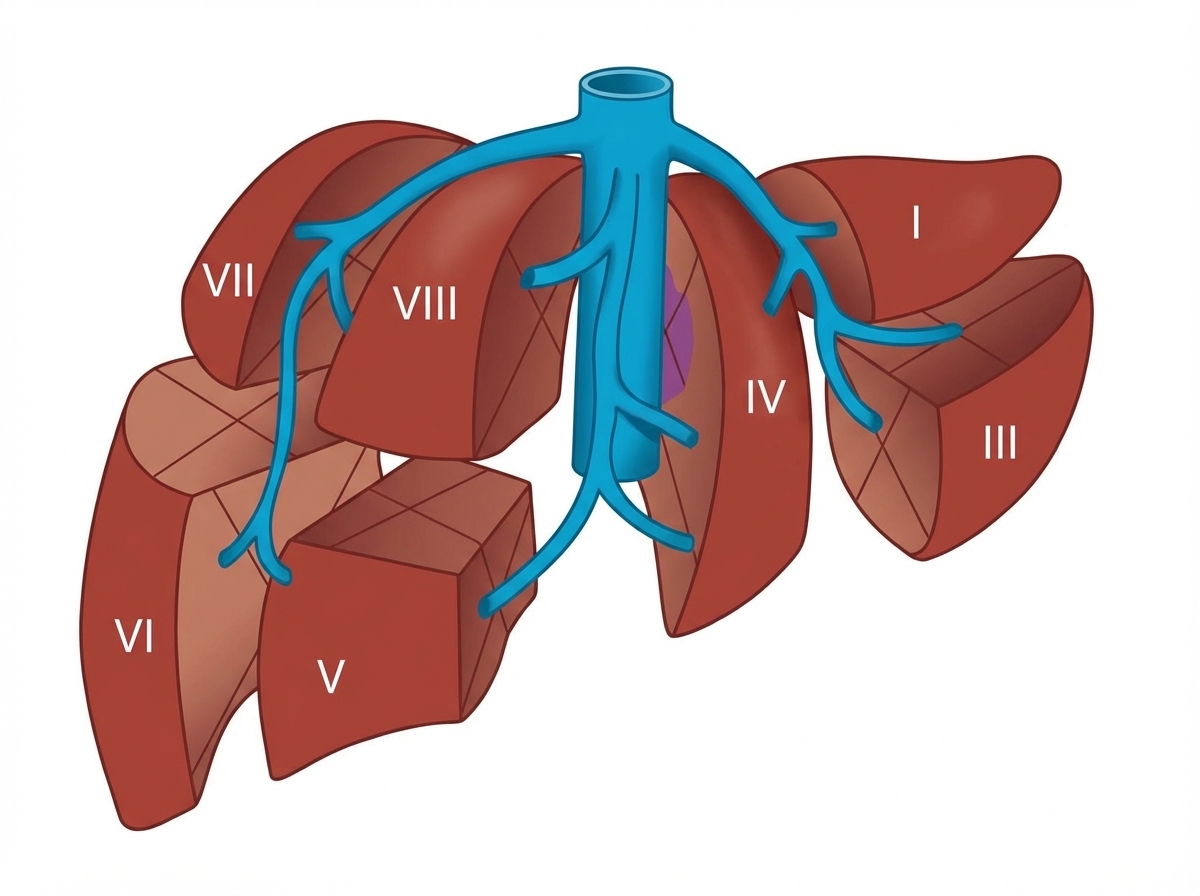

The image shows which anatomical classification system?

Explanation: ***Couinaud classification*** - This classification divides the liver into **eight functional segments** (I-VIII) based on their **hepatic venous drainage** and **portal vascular supply**. - The image shows the characteristic segmental anatomy with **hepatic veins** (right, middle, left) and **inferior vena cava (IVC)** clearly depicted, which is the hallmark of Couinaud's system. *Bismuth-Corlette classification* - This system is used for **staging hilar cholangiocarcinoma** (Klatskin tumors) based on tumor extension into bile ducts. - It focuses on **bile duct anatomy** and tumor involvement, not liver segmental anatomy as shown in the image. *Brisbane 2000 classification* - This classification system defines **hepatic resection terminology** and standardizes naming of liver resections. - It describes **resection procedures** rather than anatomical segmentation, making it unsuitable for this anatomical diagram. *Strasberg classification* - This system is used for **grading bile duct injuries** during laparoscopic cholecystectomy. - It classifies **iatrogenic bile duct injuries** into different grades, not liver segmental anatomy.